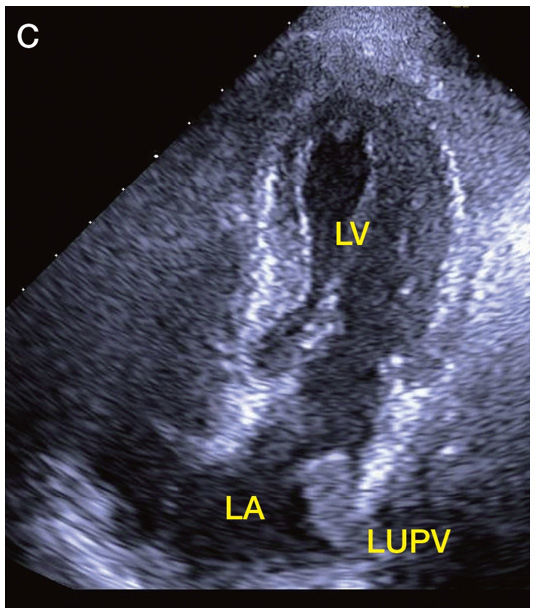

| 276 | 図5 図説 | A:右房内にIVC から伸びる異常エコーがみられる. B:症例Aの…された.子宮肉腫であり,… C:肺静脈から左房へ伸びる腫瘤が観察される.肺がんからの… |

A:右房内にIVC から伸びる異常エコーがみられる(矢印). B:症例Aの…された(矢印).子宮肉腫であり,… C:肺静脈から左房へ伸びる腫瘤が観察される(矢印).肺がんからの… |

| 276 | 図5 C | ![]() |

![]() |